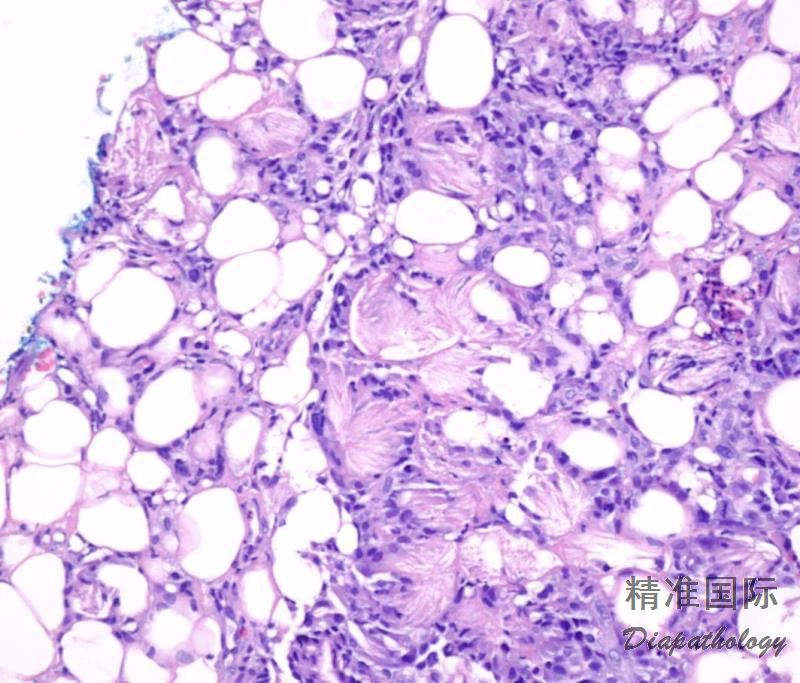

Subcutaneous Fat Necrosis of the Newborn

一般发生于出生后 1 周~6 周婴儿。病因不清。偶伴高血钙和血小板减少。 好发于背、臀、股部,坚实紫红色结节,无痛。结节数周后软化、吸收。全身健康状况尚好,大多数预后良好。

- 表皮真皮正常。

- 皮下脂肪组织小叶及间隔广泛炎细胞浸润,包括淋巴样细胞、组织细胞、异物巨细胞,残余脂肪细胞和吞噬细胞中可见放射状排列的针状裂隙。

- 坏死区有散在钙质沉积。